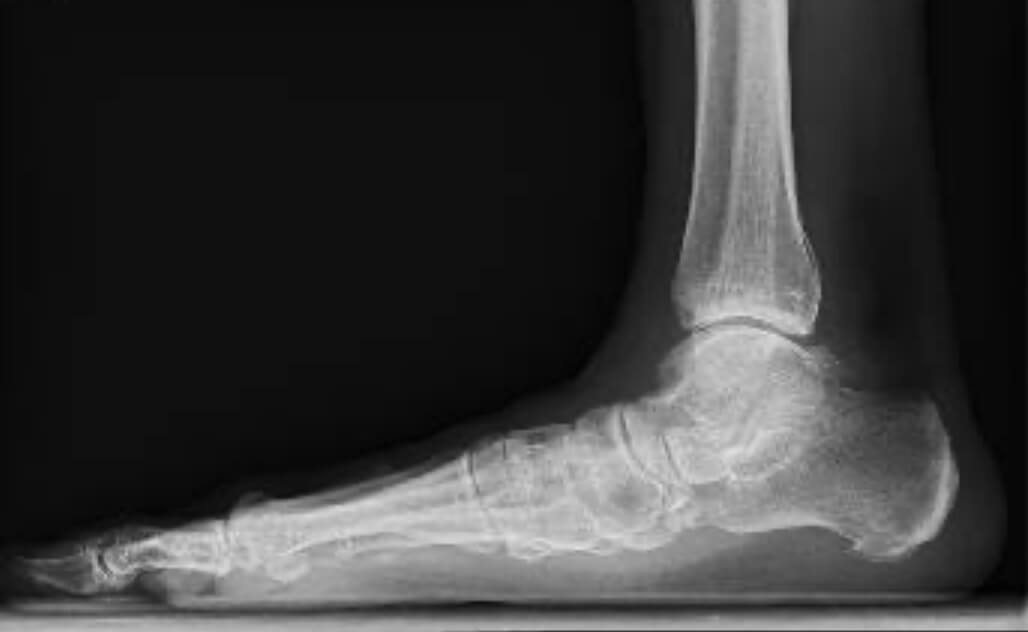

Vihdoin alkaa näkyä valoa tunnelin päässä, vaikka 4. kuukauden alkupuolella tulikin takapakkia. Pidin lääkinnällistä tukisukkaa kipulääkärin ohjeen mukaisesti siten, että vedin sukat jalkaan heti aamulla ennen kuin nousin sängystä. Näin turvotus laski, mutta samalla kipu muutti muotoaan. Sen lisäksi, että tunsin sekä jalkapöytään että nilkan ulkosyrjään asennetut implantit, nilkan ulkosyrjä kipeytyi niin pahasti, etten kyennyt enää tekemään fysioterapeutin määräämiä harjoitteita. Olin edistynyt täysin aikataulussa, mutta nyt jouduin pysähtymään. Tapasin ortopedin ja fysioterapeutin yhdessä viitisen päivää turvotuksen laskemisen jälkeen. Ortopedi sanoi, etten voi tuntea implantteja, ne ovat niin ohuita. Hän sen sijaan oletti, että nilkan ulkosyrjän kipu johtuu peroneus longus-jänteestä, joka on vihdoin joutunut töihin. Se on ollut kuin käyttämätön kuminauha jalkaholvin ollessa romahtaneena. Minun tapauksessani ainakin vuoden. Tämän minäkin ymmärsin. Kuka sitä nyt viittisi ärsyyntymättä ruveta hommiin, jos on saanut jo vuoden verran huilia.